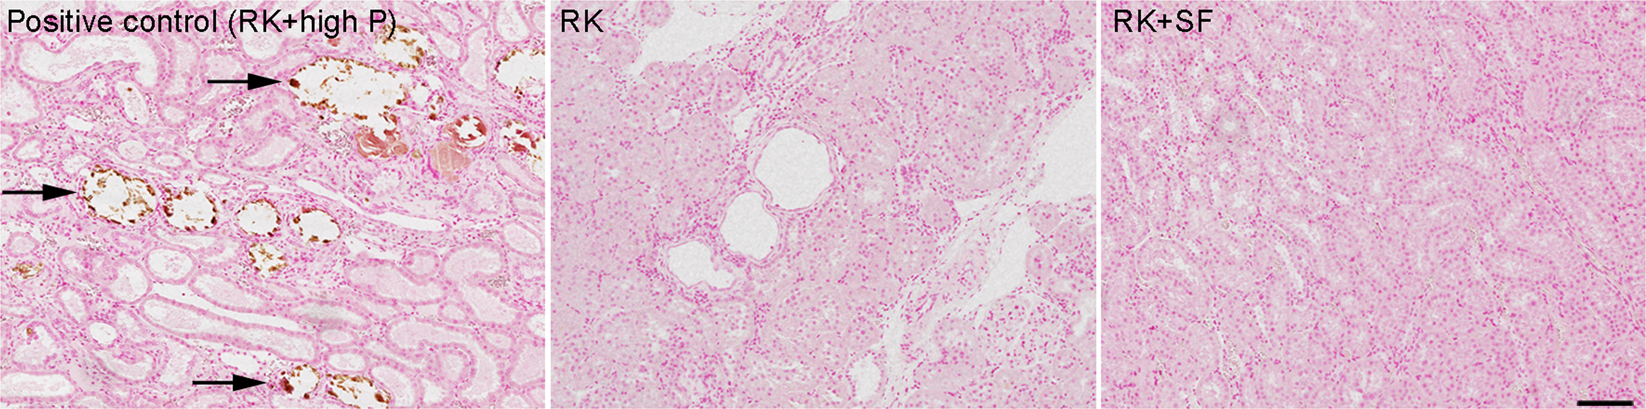

Protective effects of SF in RK rats are independent of CaPi deposition in the kidney. Representative von Kossa-stained kidney sections from RK (middle) and RK + SF rats (right). In the left panel, RK rats fed high (1.2%) phosphate diet served as a positive control for the renal calcification (indicated by arrows). Bar represents 100 μm.